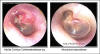

JFC Miringitis vírica flictenular.